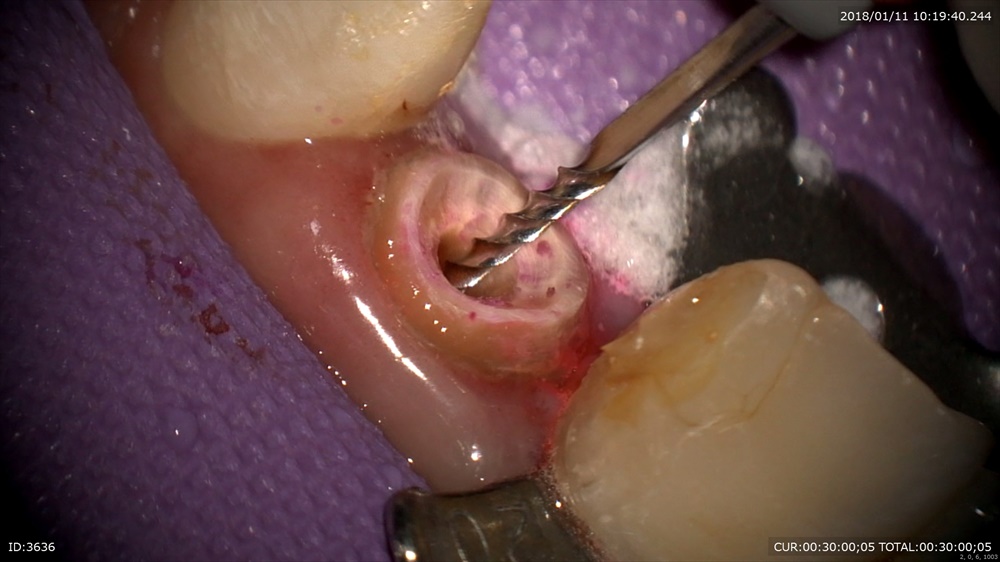

さて今日は2つ精密根管治療のご紹介

他院で根管治療中

これでは裏から感染してしまいます。

仮歯を先日作り直して

本日から精密根管治療

やはり。治らないのには理由があります。

マイクロスコープは根の先までみえます。見えるから無痛で感染を取れます。